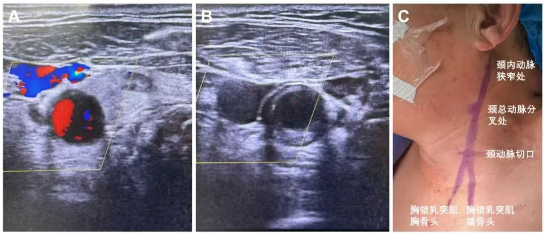

全麻后颈动脉超声标记颈总动脉切口位置、颈总动脉分叉、颈内动脉C1病变位置,确认手术切口至颈总动脉分叉距离大于5cm,颈总动脉直径大于6mm,颈内动脉直径大于4mm。

在锁骨上2-3cm,胸锁乳突肌前缘做一长约3-4cm的横向切口,逐步切开皮肤、皮下及颈阔肌,暴露颈动脉鞘,纵行切开颈动脉鞘显露颈总动脉,分别环绕皮筋,美兰标记颈动脉穿刺点。穿刺颈动脉成功,置入4F动脉鞘。同时穿刺股静脉置入静脉回流鞘管备用。

给予患者全身肝素化。造影提示右颈内动脉C1段重度狭窄,狭窄率约90%,颈总动脉长轴与颈外动脉夹角较大。通过交换技术,更换0.035in交换支撑导丝至颈外动脉远心端,经其将颈动脉-股静脉逆流管路系统放置在颈总动脉近端。夹闭颈总动脉近心端后,将管路系统与股静脉回流鞘连接,确认无气泡后建立颈动脉-股静脉逆流通路。经管路系统近端Y型鞘送入0.014 in微导丝至颈内动脉C1段远端,经其送入5.0mm *30mm球囊扩张病变。撤出球囊,放置9.0mm*30mm自膨式闭环颈动脉支架,完全覆盖病变。撤出微导丝及支架推送系统后,继续维持颈动脉-股静脉逆流2min。松开颈总动脉阻断夹,术中颈总动脉夹闭时长9min。造影显示颈动脉残余狭窄率约10%,大脑中动脉及大脑前动脉未见异常。撤出管路系统,荷包缝合颈总动脉穿刺点,逐层缝合颈动脉创面。